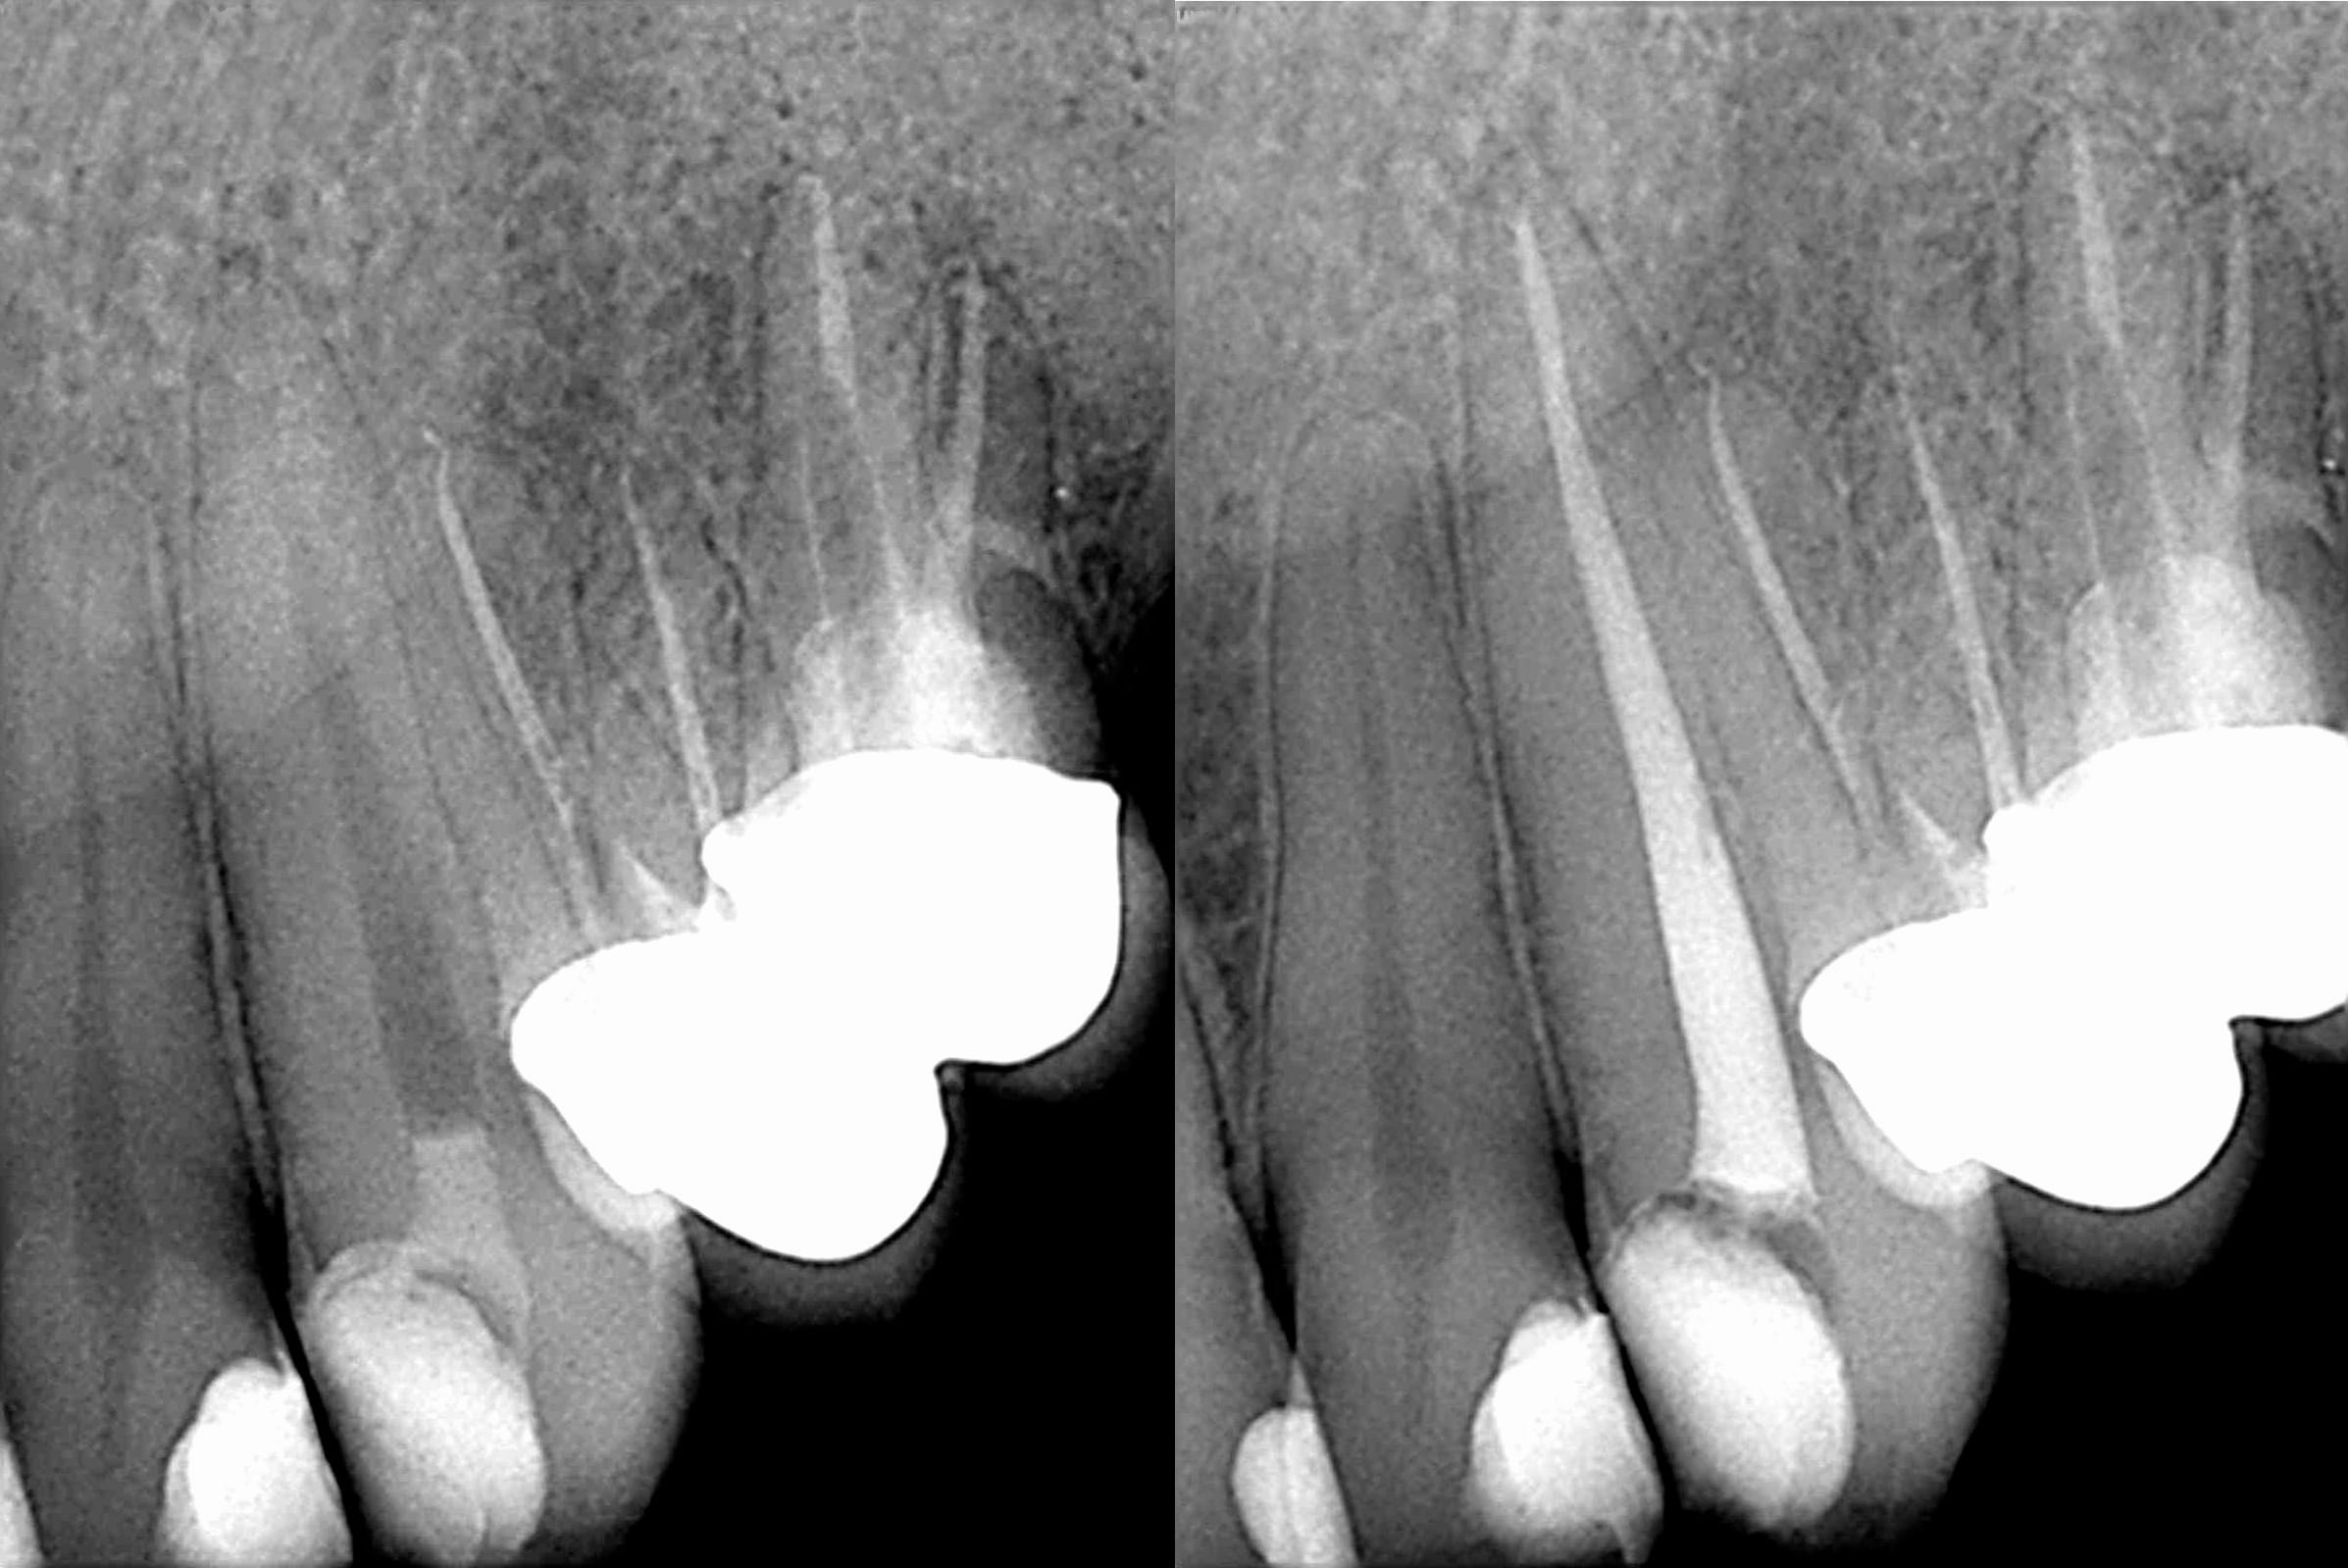

- The dental cyst will occupy a space in the jaw and may displace or replace normal tissues.

- Dental cysts may resorb (eat into) adjacent teeth or push the teeth out of their normal alignment.